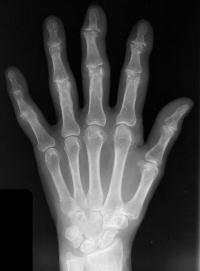

Second case.

This patient had previous experience with both DIP fusion and PIP arthroplasty.

Ring finger DIP joint of the opposite hand.

Xrays one year out.